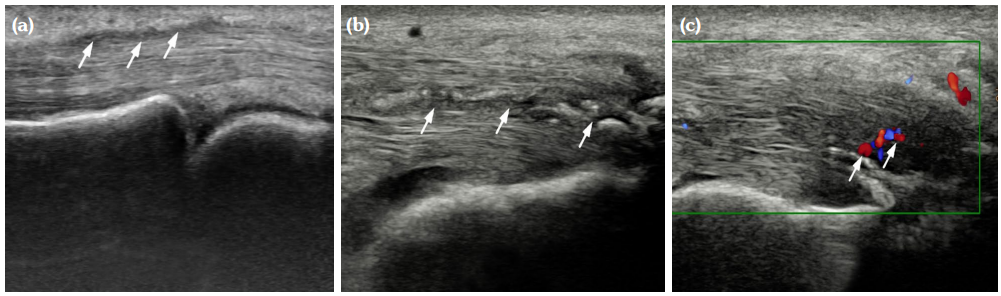

The degree of BE and synovial hyperplasia in SNRA or SPRA is more serious, and the blood flow signal is more abundant. However, the degree of synovial hyperplasia in osteoarthritis was mild, and no obvious blood flow signal was detected (Figures 1, 2, 3 and 4). Magnetic resonance imaging (MRI) studies of SPRA also showed serious BE (Figure 5).

Among SNRA, SPRA and non-RA, there was no significant difference in the grades of SH, PD, BE, nor the number of cases of tendinitis and tenosynovitis between the SNRA group and the SPRA group (p>0.05) (Table 3). There were, however, statistically significant differences in the number of cases of SH1, SH3, PD and BE grades between the SNRA and non-RA groups (p<0.001). There was no significant difference in the number of cases of SH2, PD2, tendinitis or tenosynovitis between the SNRA and non-RA groups (p>0.05) (Table 4).

Our findings suggest that the use of synovial blood flow and the degree of BE are helpful in distinguishing RA from non-RA, which may be explained by the underlying pathological changes. The pathological features of RA include primary synovial inflammation, which produces aggressive synovial pannus attached to the cartilage, causing hypoxia and erosion of the bone. Synovitis caused by non-RA disease is mostly due to inflammation, edema and thickening of synovium due to degenerative or pathological changes of cartilage and cortical bone. It is not difficult to understand that the invasive synovial blood vessels during RA are closely related to the phenomenon of BE; thus, the combination of the two ultrasonic characteristics are sound pathological indicators for the evaluation of RA.